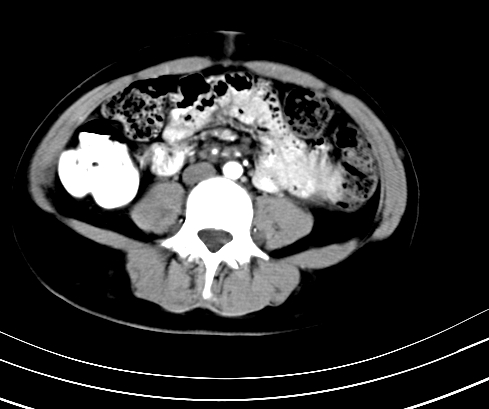

标题: CT23915:女 20岁 全身长疙瘩三年 今日多体位查 看看吧 [打印本页]

标题: CT23915:女 20岁 全身长疙瘩三年 今日多体位查 看看吧

静脉期

延时5分钟

延时10分钟

神经纤维瘤病

支持神经纤维瘤。

支持 神经纤维瘤病。